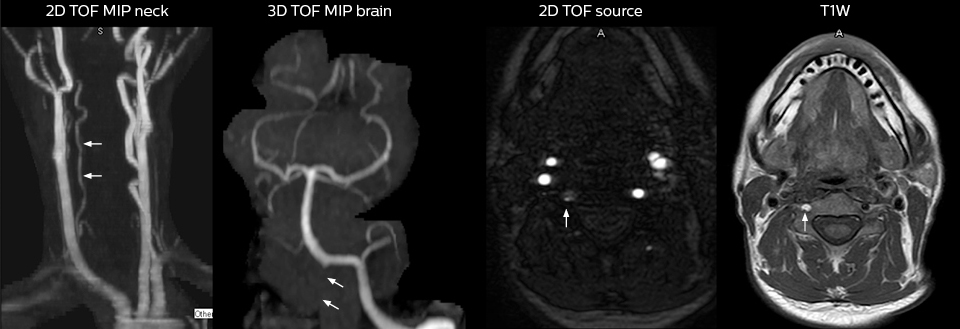

To minimize the time taken to perform scans, rapid MRI examination protocols (ExamCards) were developed, shortening the total scanning time to even less than 10 minutes in some exams. Techniques like mDIXON (modified DIXON) are used for robust capturing of fat-free MRI images in a hectic ED environment.

“We use mDIXON TSE extensively in our spine imaging in the emergency room,” says Dr. Karis. “It’s particularly nice in that it is very robust with regard to susceptibility type of problems that would come up with traditional spectral fat-saturated images; these problems are essentially eliminated with the mDIXON technique. In our ED environment it’s really nice to have the fat-free imaging that goes along with the mDIXON technique.